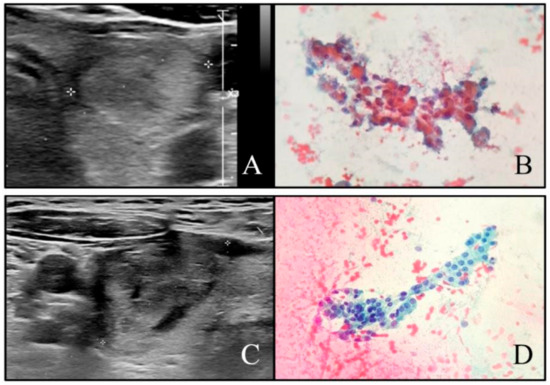

2.2. Ultrasound Evaluation

2.3. Cytopathology and Histopathology